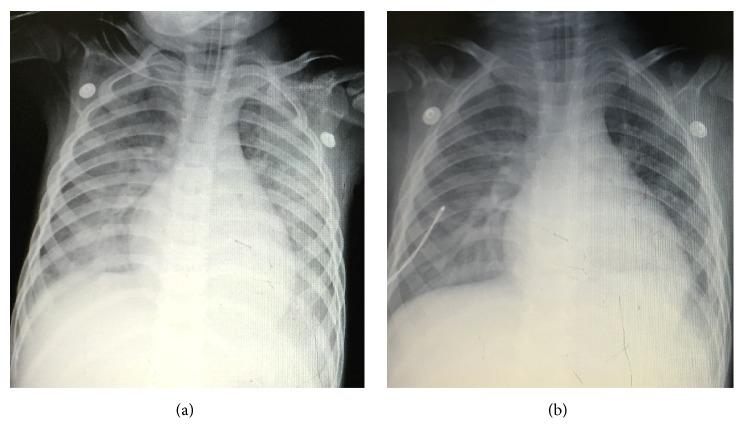

Critical care ultrasound (CCUS) has been widely used as a useful tool to assist clinical judgement. The utilization should be integrated into clinical scenario and interact with other tests. No publication has reported this. We present a CCUS based "7-step approach" workflow-the PIEPEAR Workflow-which we had summarized and integrated our experience in CCUS and clinical practice into, and then we present two cases which we have applied the workflow into as examples. Step one is "problems emerged?" classifying the signs of the deterioration into two aspects: acute circulatory compromise and acute respiratory compromise. Step two is "information clear?" quickly summarizing the patient's medical history by three aspects. Step three is "focused exam launched": (1) focused exam of the heart by five views: the assessment includes (1) fast and global assessment of the heart (heart glance) to identify cases that need immediate life-saving intervention and (2) assessing the inferior vena cava, right heart, diastolic and systolic function of left heart, and systematic vascular resistance to clarify the hemodynamics. (2) Lung ultrasound exam is performed to clarify the predominant pattern of the lung. Step four is "pathophysiologic changes reported." The results of the focused ultrasound exam were integrated to conclude the pathophysiologic changes. Step five is "etiology explored" diagnosing the etiology by integrating Step two and Step four and searching for the source of infection, according to the clues extracted from the focused ultrasound exam; additional ultrasound exams or other tests should be applied if needed. Step six is "action" supporting the circulation and respiration sticking to Step four. Treat the etiologies according step five. Step seven is "recheck to adjust." Repeat focused ultrasound and other tests to assess the response to treatment, adjust the treatment if needed, and confirm or correct the final diagnosis. With two cases as examples presented, we insist that applying CCUS with 7-step approach workflow is easy to follow and has theoretical advantages. The coming research on its value is expected.

重症超声(CCUS)已广泛应用于辅助临床判断的有用工具。这种应用应该整合到临床情况中,并与其他测试相互作用。目前还没有出版物报道过这一点。我们提出了一种基于 CCUS 的“7 步方法”工作流程——PIEPEAR 工作流程,我们将其总结并整合了我们在 CCUS 和临床实践中的经验,然后提供了两个应用该工作流程的案例作为示例。第一步是“问题出现了吗?”将恶化的迹象分为两个方面:急性循环衰竭和急性呼吸衰竭。第二步是“信息明确吗?”通过三个方面快速总结患者的病史。第三步是“启动重点检查”:(1)通过五个视图进行心脏重点检查:评估包括(1)快速全面评估心脏(心脏扫查),以确定需要立即进行救生干预的病例,以及(2)评估下腔静脉、右心、左心舒张和收缩功能以及系统性血管阻力,以明确血液动力学。(2)进行肺部超声检查以明确肺部的主要模式。第四步是“报告病理生理变化”。将重点超声检查的结果整合起来,总结病理生理变化。第五步是“探索病因”,通过整合第二步和第四步,并根据重点超声检查中提取的线索,寻找感染源,诊断病因;如果需要,应应用额外的超声检查或其他测试。第六步是“行动”支持循环和呼吸,坚持第四步。根据第五步治疗病因。第七步是“复查调整”。重复重点超声和其他测试,以评估治疗反应,根据需要调整治疗,并确认或纠正最终诊断。通过呈现两个案例,我们坚持认为,应用 7 步方法工作流程进行 CCUS 易于遵循,并且具有理论优势。预计未来将对其价值进行研究。